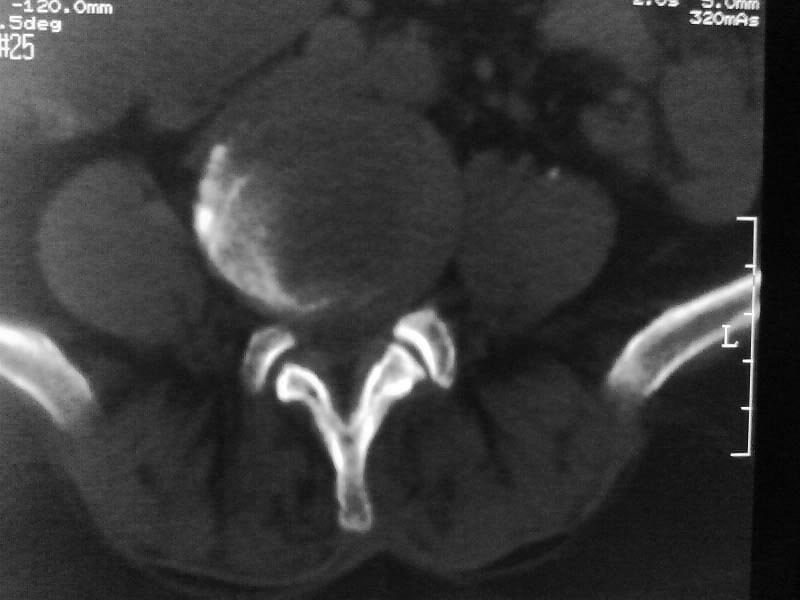

定位相示l2呈楔形改变(ct示陈旧性骨折改变,图像未传),l4.5椎体融合,以下是l4.5ct平扫.请各位看看,

考虑结核(有破坏、硬化及死骨)。

1、三四椎体结核,2、水平骶椎。

1、l1压缩性骨折(陈旧性)。

2、l3、4椎体结核。

就是腰1压缩性骨折,腰3\\4椎体结核(融合),水平骶椎.

支持 l1椎体陈旧性压缩性骨折;l3、4椎体结核(融合);水平骶椎。